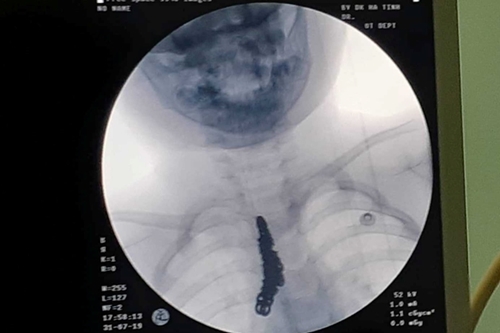

Phim chụp hình chiếc lắc tay nằm trong khí quản của cháu bé - Ảnh: Infonet. |

Theo báo Bảo vệ pháp luật, sau khi thăm khám và chụp phim X-quang, các bác sỹ phát hiện hình ảnh cản quang bất thường tương ứng khí quản và một phần phế quản gốc bên phải.

Ngay lập tức bệnh nhi được chuyển thẳng lên khoa Gây mê hồi sức, tại đây Kíp thủ thuật đã nhanh chóng triển khai nội soi khí quản phát hiện dị vật nằm ở khí quản và phế quản gốc bên phải. Các bác sĩ đã tiến hành gắp ra được 1 sợi dây chuyền bạc có kích thước dài 14cm.